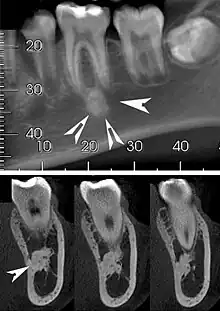

| Top: A hyperdense round lesion located under the apex of a non-infected tooth. Bottom: The lesion is separated from the root of the adjacent tooth by a visible periodontal membrane.[1] | |

Idiopathic osteosclerosis, also known as enostosis or dense bone island, is a condition which may be found around the roots of a tooth, usually a premolar or molar.[2] It is usually painless and found during routine radiographs as an amorphous radiopaque (light) area around a tooth. There is no sign of inflammation of the tooth, and if the island is associated with the root the periodontal ligament space is preserved.[2]

Well defined, rounded or triangular radiodensity, that is uniformly opaque. There is no lucent component. Found near the root apex or in the inter-radicular area. Root resorption and tooth movement are rare. If it blends into bone cortices, it does so with no expansion or thinning.[2]